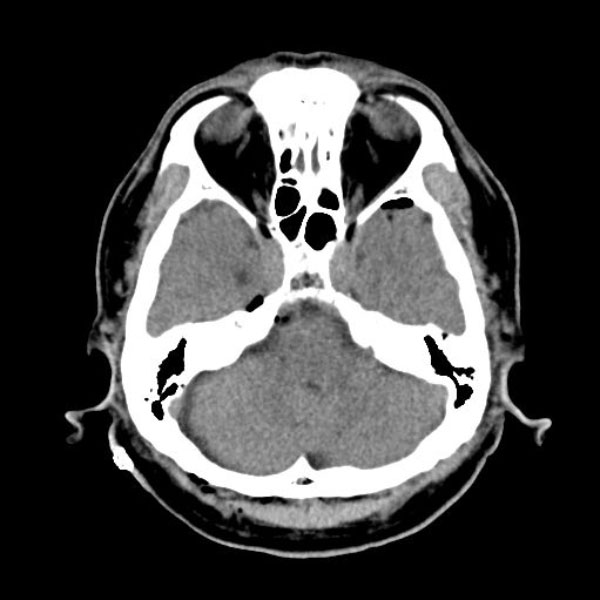

手術前

(MR1)

手術後

(CT)